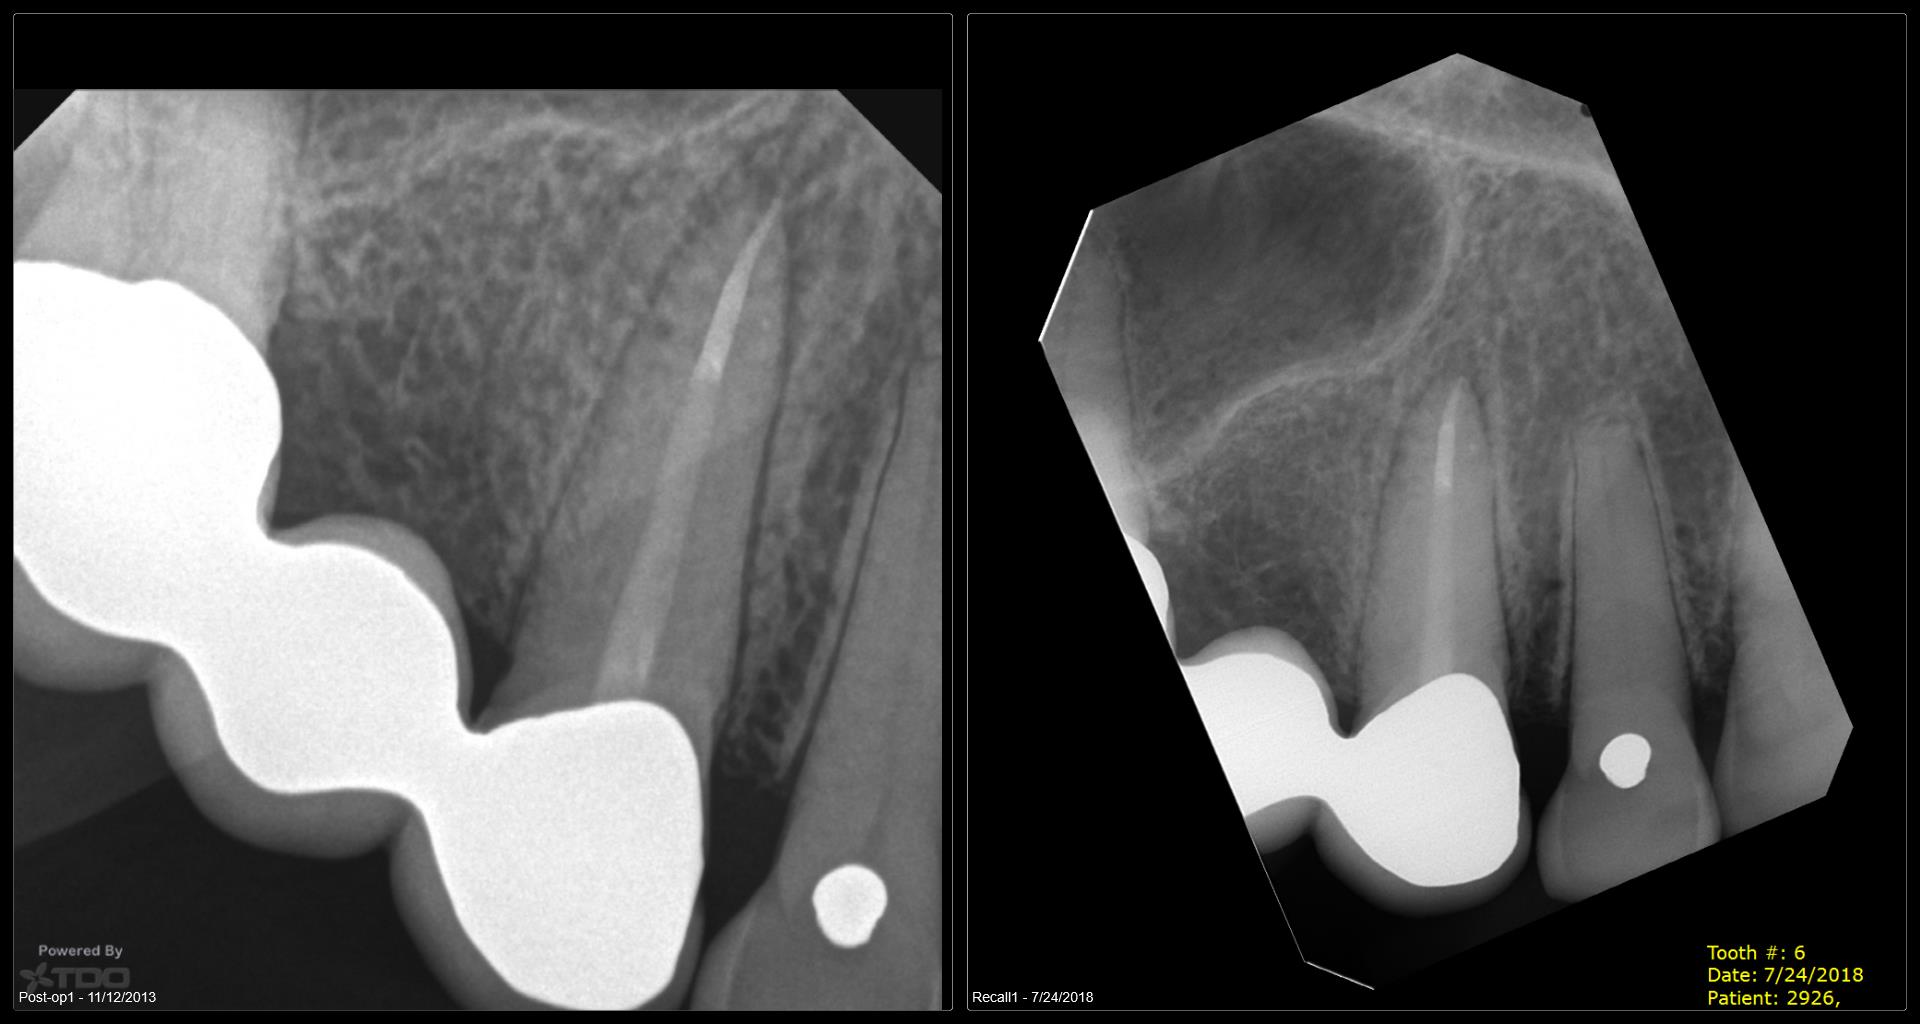

5 yr CBCT recall

Entire buccal plate missing. CBCT at 5 years suggests most, but not all, bone has regenerated. As canine bridge abutment, it is subjected to some occlusal trauma. gbc